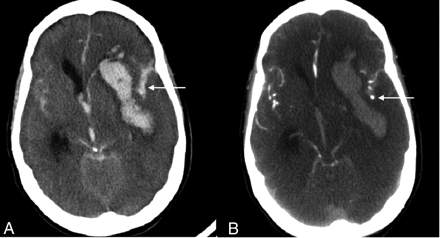

Where is the aneurysm likely to be in this patient?

The location of the haemorrhage can help localise the site of the ruptured aneurysm.

Anterior Comm Artery Aneurysm:

MCA aneurysm: (previous case)